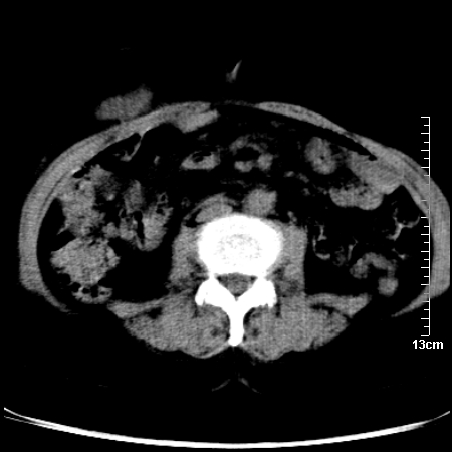

巨大囊实性包块,边界大部尚清楚,不太像脓肿的表现。应该做个增强检查除外盆腔肿瘤。

如果能进行肠道准备就好了!盆腔内巨大囊实性包块,右前缘与周围肠管分界不清,病灶内前部的气体是否为肠管内气体形成的假象不能确定。

这么大一包快手术当中没有发现?值得怀疑!结合化脓性阑尾炎病史,首先考虑脓肿!不排外附件来源的肿瘤,建议增强扫描!!

因术前未做相关检查,故漏诊完全有可能!若脓肿这么大,临床不会单纯是阑尾炎的体征!支持:盆腔肿瘤——首选:附件来源的肿瘤,建议增强扫描!!!

这么大的肿块术中会发现不了啊,不过现在病灶的样子比较支持肿瘤,有没有可能子宫肌瘤?